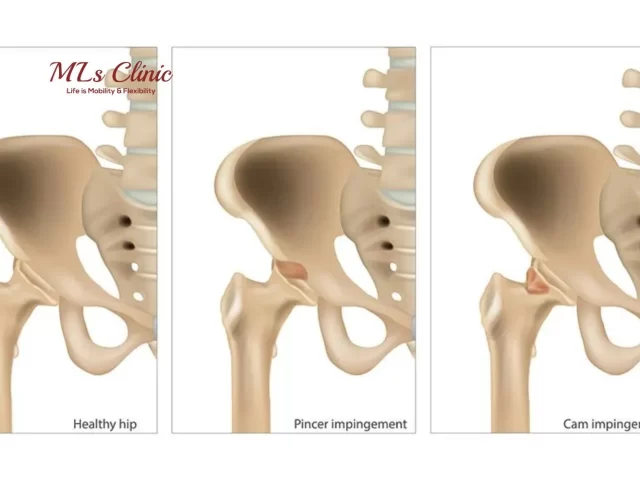

Hip Impingement (FAI) in Young Adults- Symptoms and Surgical Treatment

Hip pain is no longer just a concern for the elderly. Increasingly, young adults are reporting hip discomfort and restricted...